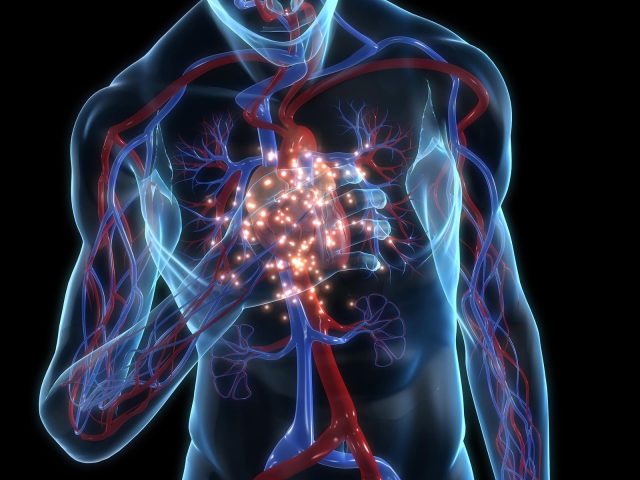

Akciğer Embolisi (Pulmoner Emboli), derin bacak toplardamarlarında oluşan pıhtının(trombüs), oluştuğu yerden koparak akciğer atardamarını tıkamasıyla oluşan bir hastalıktır. Ani başlangıçlı göğüs ağrısı ve nefes darlığı ile belirti veren Akciğer Embolisi, bacaktaki pıhtıdan kopan parça ya da parçaların, boyutuna göre akciğer atardamarının ana gövdesinde, dallarının bir veya birkaçında tıkanmaya sebep olarak ani ölümlere sebep olabiliyor. Ana damarlardan biri tıkandığında ise gelişen durum “Masif Pulmoner Emboli” olarak adlandırılıyor ve hastalar için durum oldukça ciddi boyutlara ulaşabiliyor.

Akciğer Embolisi’nin, başta akciğerler ve kalp olmak üzere birçok organın çalışmasını etkilediğini ve hayati riskin çok yüksek olduğunu belirten Acıbadem Fulya Hastanesi Kalp ve Damar Cerrahisi Uzmanı Doç. Dr. Cem Arıtürk, “Hastalığın kaynağı hemen tüm vakalarda Derin Ven Trombozu(DVT)’dur. Bacak derin toplardamarlarında oluşan kan pıhtısı, olduğu yerden koparak akciğer atardamarını tıkar ve Akciğer Embolisi’ne sebep olur. Bu yüzden DVT geçirmiş kişiler, Akciğer Embolisi açısından da risk altındadırlar. Bunlar haricinde kırık kemiğin iliğinde bulunan yağlı madde, hamilelik, doğumda amniyotik sıvı ve madde kullanımı nadir de olsa hastalığa sebep olabilen durumlardır” dedi.